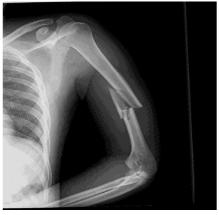

(58.2%) patients. The distribution of enrolled patients is depicted in Fig 1.Among the presenting complaints, fever was the most common (n=145, 88.4%), followed by weight loss (n=130, 79.2%), cough (n=90, 54.8%), night sweats (n= 50, 30.4%), shortness of breath (n=25, 15.2%), and abdominal pain (n=16, 9.7%). Anemia with Hb< 12 g/dL was present in 69.5% patients (n=114) .

Fig 1 — Distribution of enrolled patients in the study